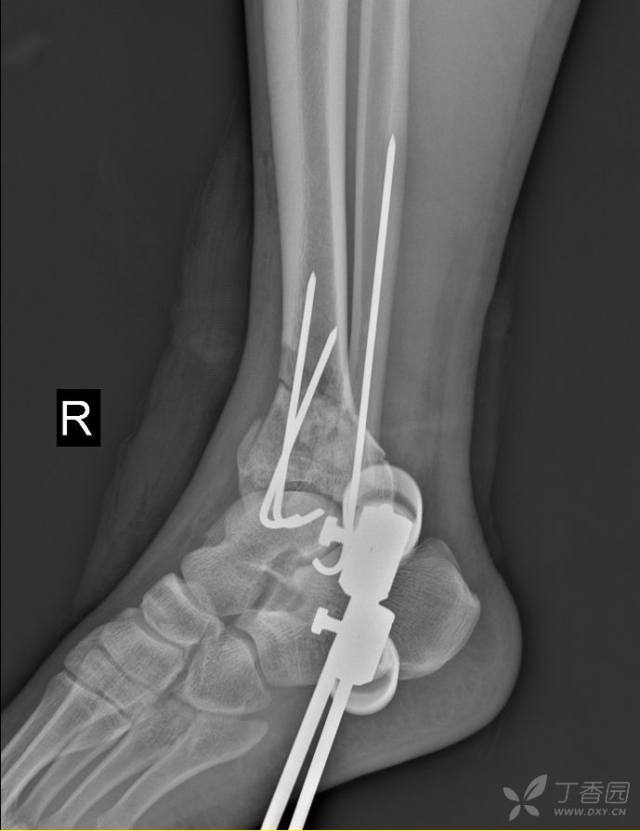

踝关节骨折 健康号 微医

足首脱臼骨折入院5 7目 足関節観血的手術 激痛 リハビリ開始 ひにログ